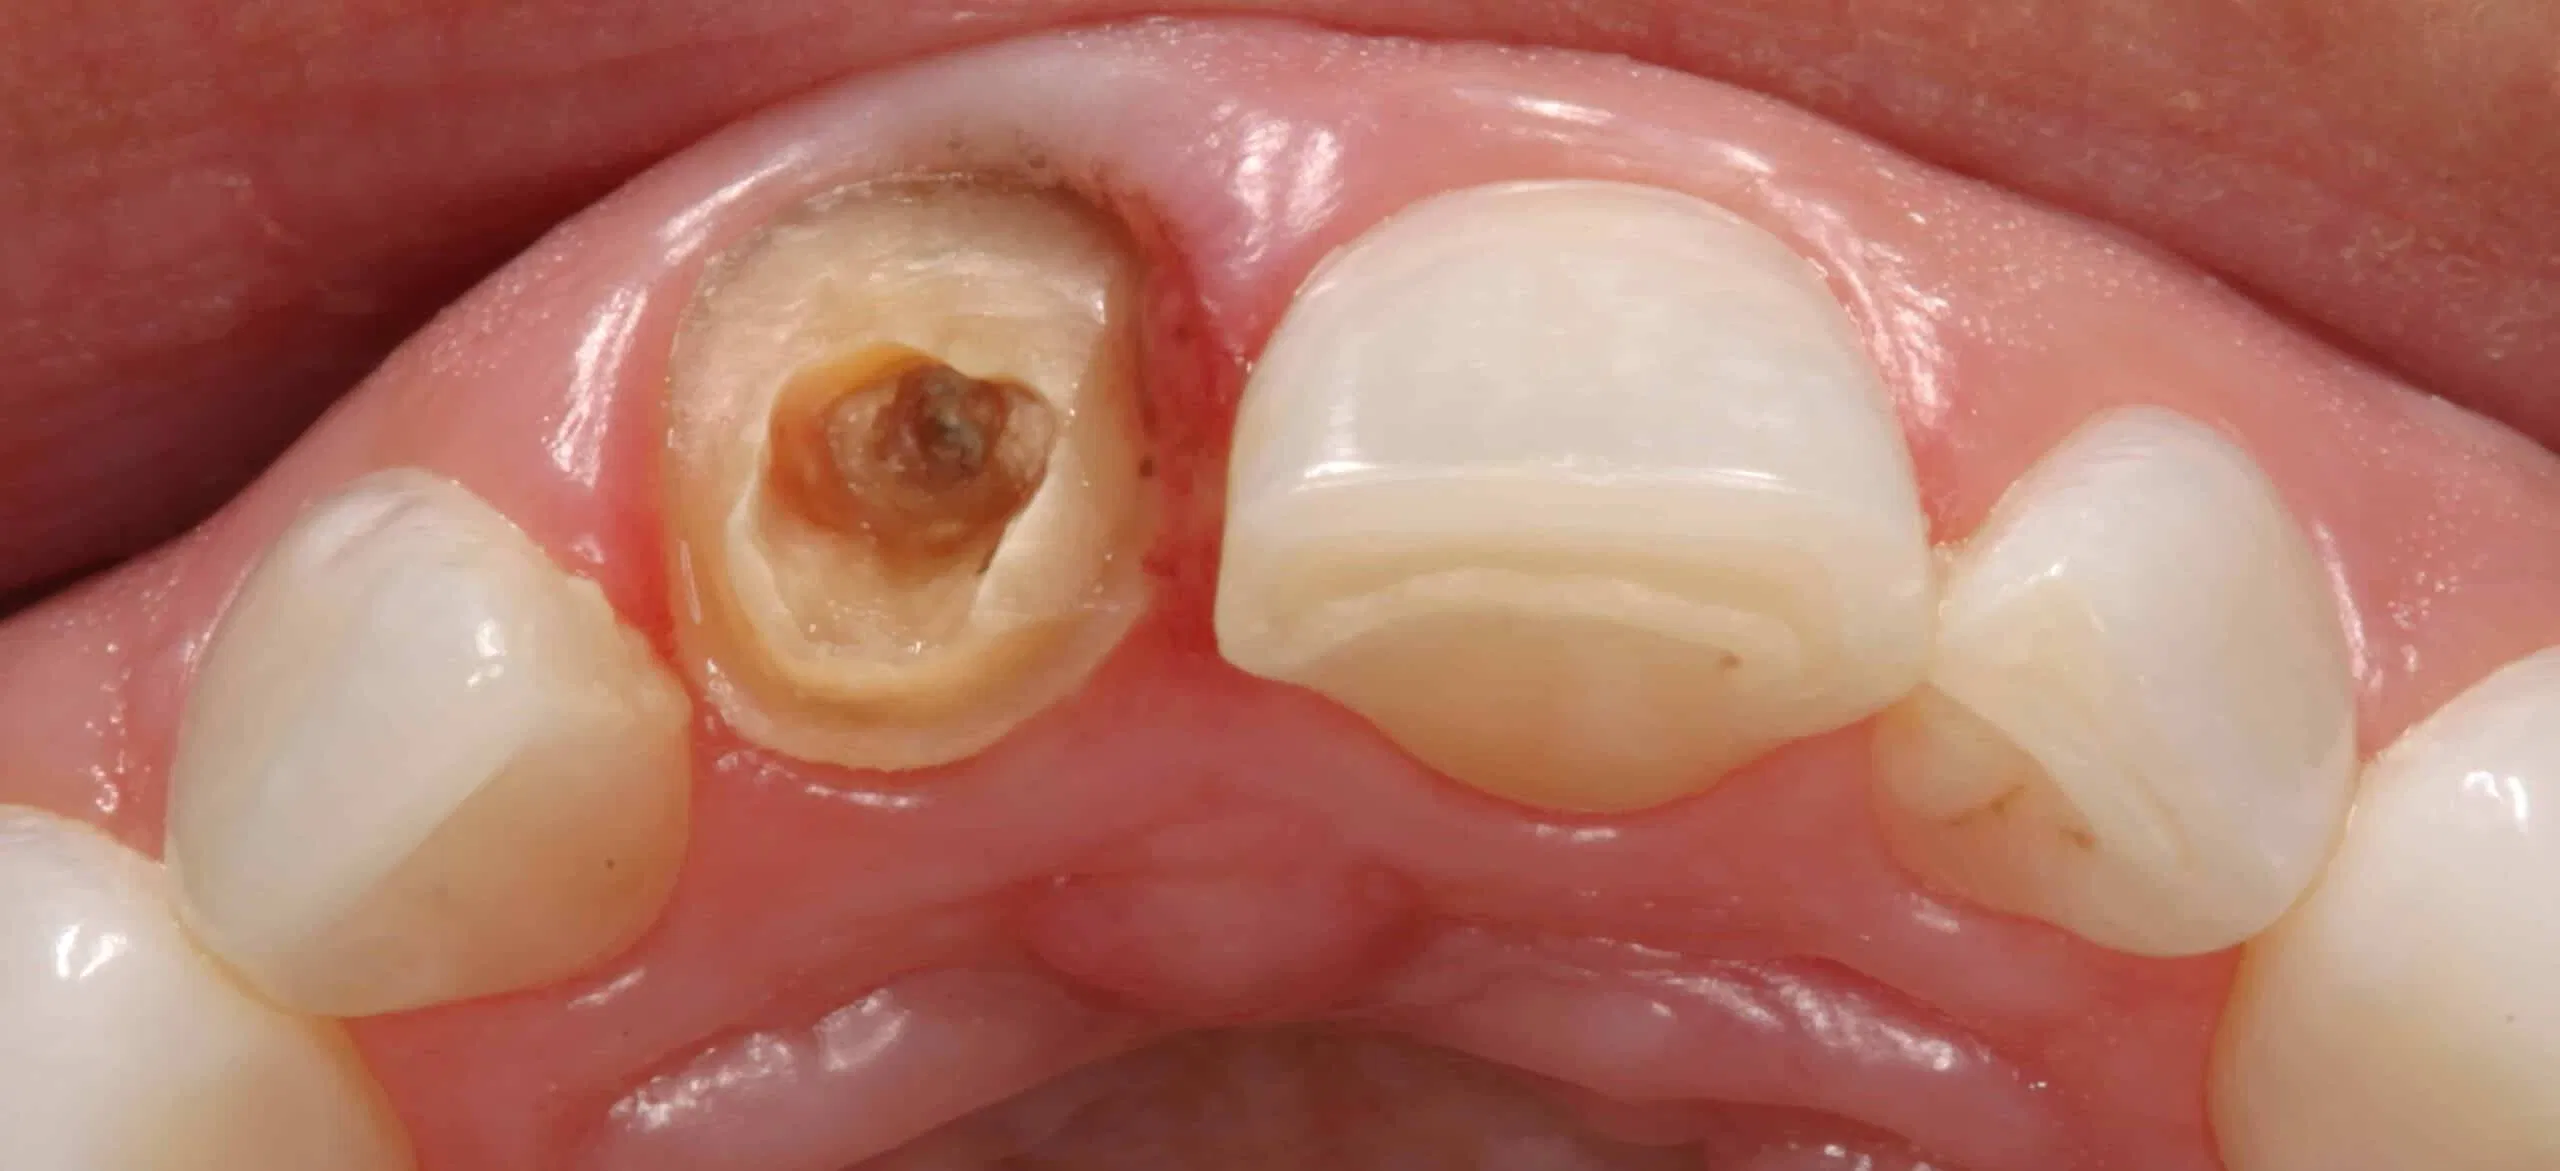

Before:Â Fractured/failed heavily treated upper right central incisor (tooth #8). The root is non-restorable and requires removal. The treatment of choice is a single implant supported restoration.

After: Single, all-ceramic crown attached to an all-ceramic, CAD-CAM designed and generated abutment (implant post). A delayed treatment approach was undertaken: tooth/root removal and grafting; 4 months healing; interim removable partial tooth replacement; implant placement; 6 months healing; proto-type (transitional fixed) implant crown, then the definitive implant restoration. The new tooth blends in perfectly with the natural, adjacent teeth.